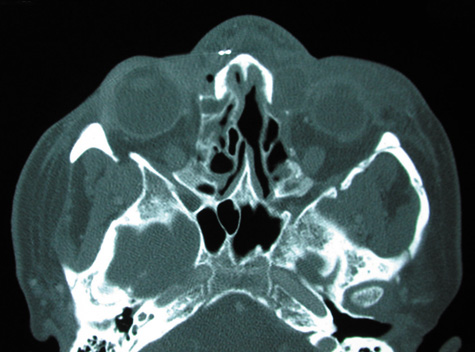

Routine skull films and polytomography have been supplanted by CT in the evaluation of patients with orbital cellulitis.57 CT allows the clinician to differentiate a preseptal cellulitis from an orbital cellulitis.58 If orbital cellulitis has resulted from adjacent intercurrent sinus infection, the diagnosis can be made and the extent of the sinus disease estimated. Sinuses may show changes of osteomyelitis with blurring of the osseous margins of the sinuses, air–fluid levels, or inflammatory tissue within the normally aerated sinus.59 Central nervous system complications can be assessed by neuroimaging, and progression of disease can also be monitored.58

CT should be performed using thin-section (2–4 mm) high-resolution scanning with multiple views of both bone and soft tissue detail.53 Axial and coronal views should be obtained; in one-third of patients with subperiosteal abscesses, the abscess was seen in the coronal sections only.18 Helical CT is a fairly new technology that allows increased resolution with decreased imaging time.60 This type of scan may be especially beneficial in children because of the ability to obtain good imaging with a shorter imaging time.60 elica He HhIntravenous contrast material is not advocated at all centers because there is intrinsically high contrast between infectious changes and orbital fat. However, some authors believe that it is essential to the diagnosis, and it thus remains the preference of the individual clinician, as well as the neuroradiologist.22,59,62

With preseptal inflammation, CT demonstrates soft tissue swelling of the eyelids and tissue adjacent to the orbital septum (Fig. 15). The orbit is not involved, and usually the sinuses do not show evidence of inflammation. The distinction between inflammatory preseptal cellulitis and edema cannot be made.63

Fig. 15. Computed tomography showing preseptal cellulitis of left eye. Note that all swelling is anterior to the orbital septum.